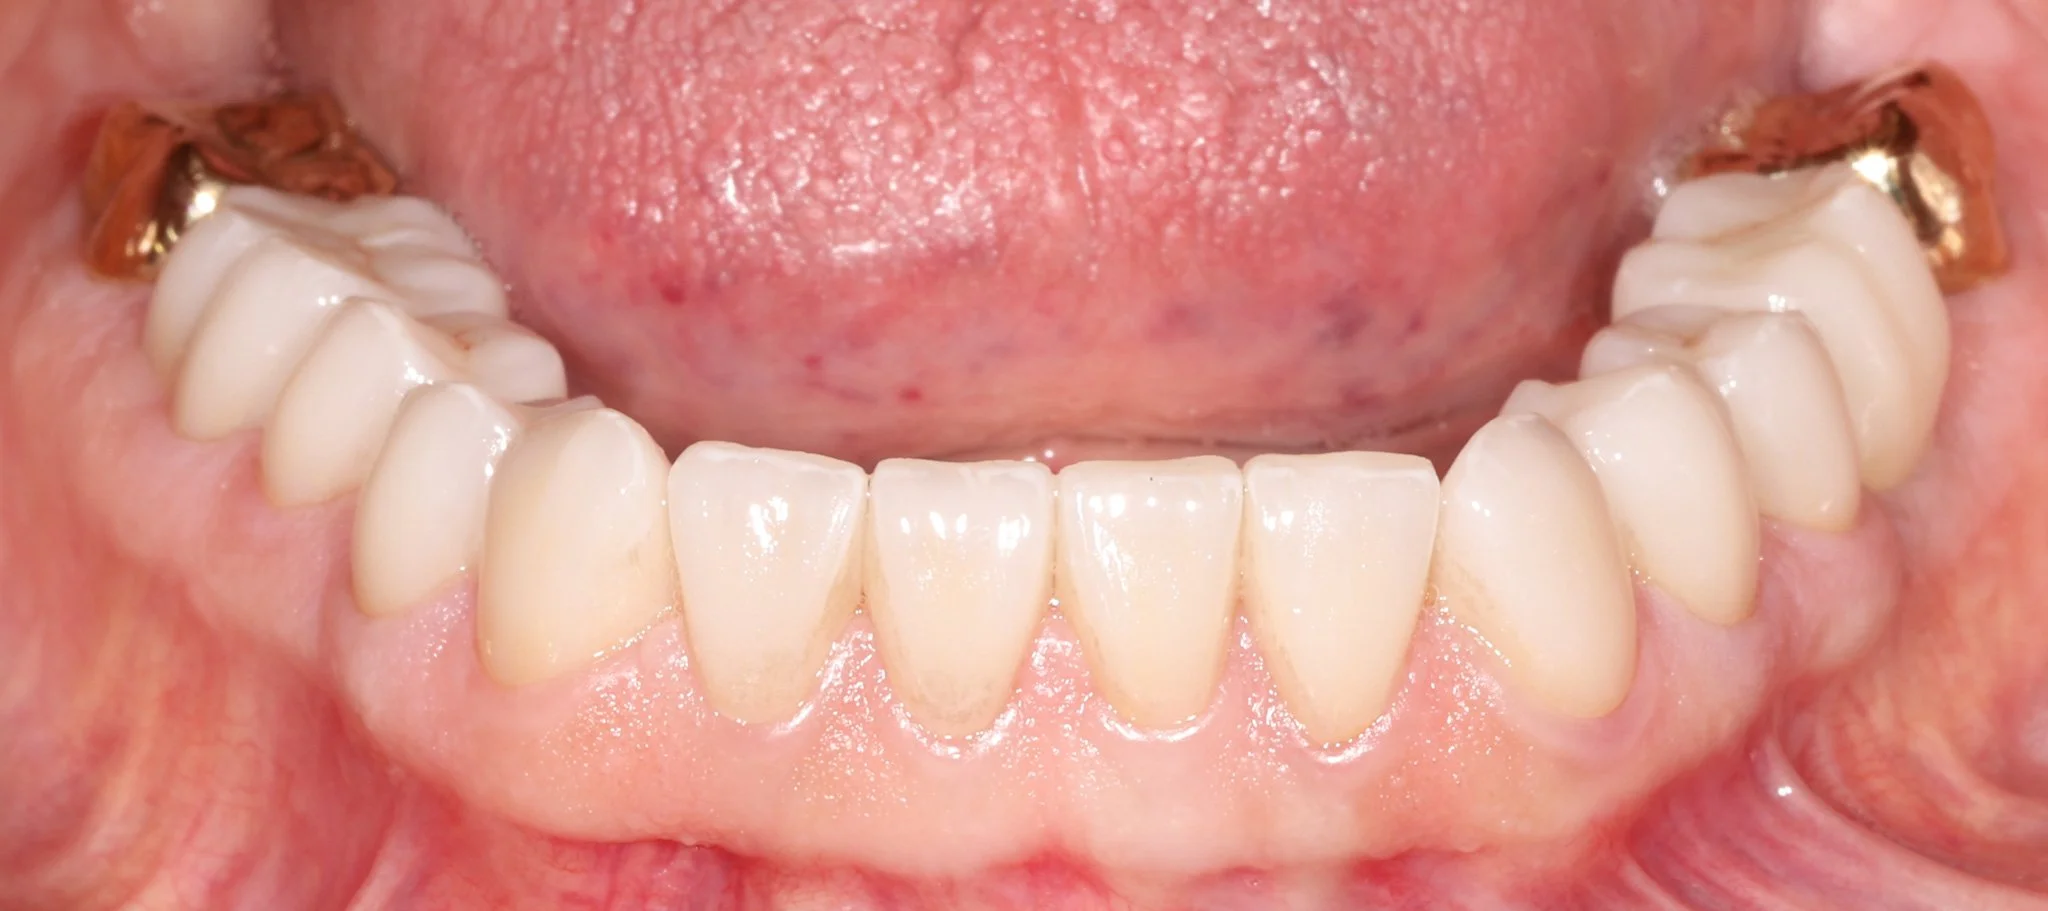

A patient's teeth after restoring with bonded porcelain and gold restorations.

After: Bonded porcelain and gold restorations to restore what was lost